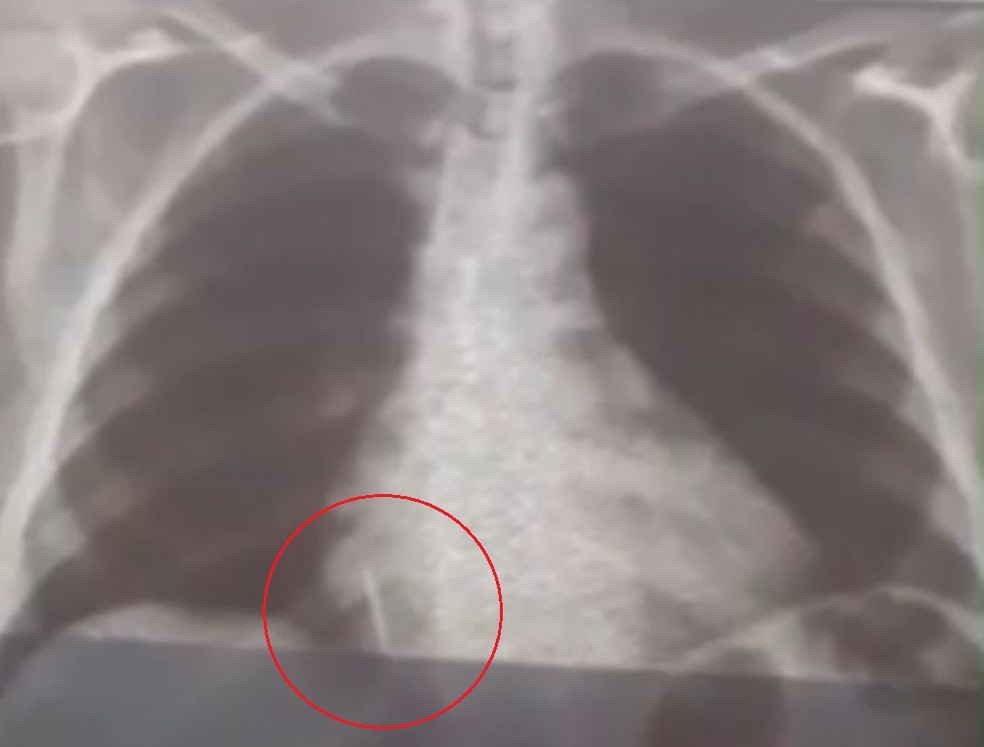

Broca de dentista se solta durante atendimento e vai parar dentro de pulmão de paciente no RN

Foto: Reprodução

Uma paciente de 55 anos engoliu uma broca durante a extração de um dente em uma unidade de saúde no município de Lajes, Região Central potiguar. O caso aconteceu no dia 26 de julho.

Iolanda Mariano de Melo Simplício está com o material alojado no pulmão deste então. O filho dela conta que a mãe sente muitas dores e já perdeu cerca de 10 quilos desde o ocorrido.

“A Secretaria Municipal de Saúde nos deu assistência para a realização dos exames. A gente foi para Natal inúmeras vezes com ela para fazer tomografia, raio-x, hemograma, risco cirúrgico, mas até agora nada. Já são quase 29 dias e praticamente não temos resposta. A gente quer uma solução, porque é um corpo estranho que está dentro do pulmão dela”, conta Rohnhalyson Mariano.

A Prefeitura de Lajes informou que a cirurgia da paciente chegou a ser marcada para 11 de agosto, mas não aconteceu pois um dos equipamentos necessários para o procedimento quebrou.

O município informou que está se preparando para realizar a cirurgia de forma particular. A Prefeitura está analisando os orçamentos e vai pagar pelo procedimento de retirada do objeto do pulmão da paciente.

De acordo com a secretaria municipal de saúde, o dentista responsável pelo acidente foi afastado e não voltará a trabalhar no município, que já providencia um profissional substituto.